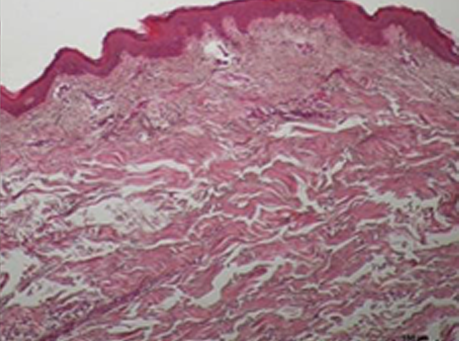

콜라겐 활성의 변화

ONDA 시술 후 진피의 콜라겐이 활성화 되었음을 알 수 있고, ONDA의 에너지가 열로 변환되면서

늘어져 있던 콜라겐을 수축시키고 리모델링을 통해 스킨 타이트닝과 리프팅 효과가 동시에 있음을 확인할 수 있습니다.